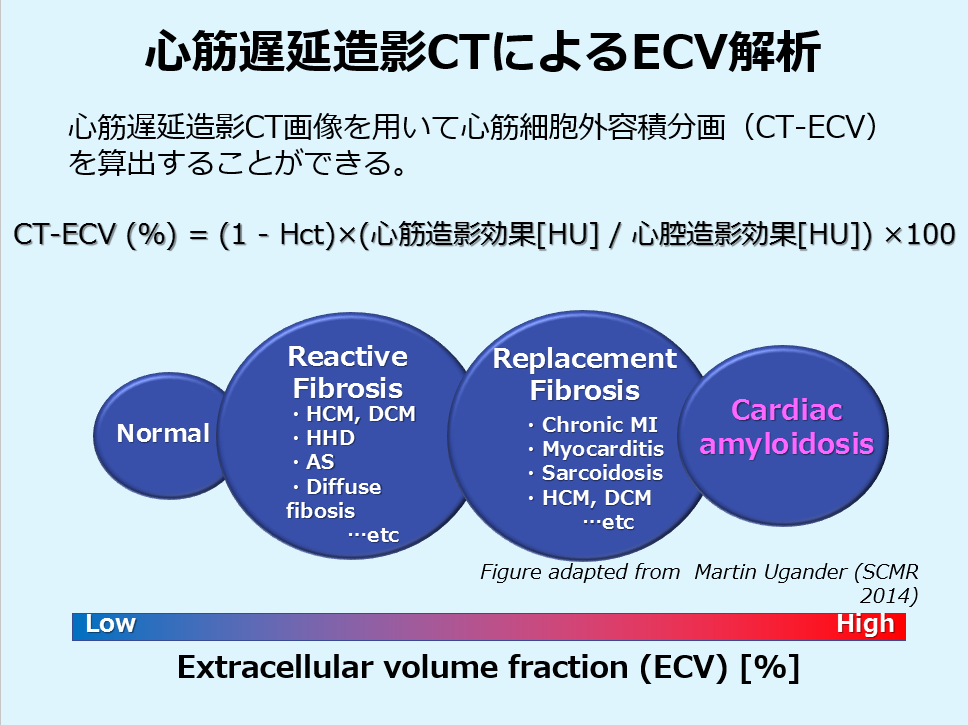

心筋遅延造影CTを撮影することで、MRIでの心筋ダメージの指標として確立している細胞外容積分画(ECV)をCTから算出することができます。

ECV50%と極端な異常値を呈しており、心アミロイドーシスを疑う所見でした。

視覚的な遅延造影は淡いコントラストであり、評価が難しい。ECV解析にて明らかな異常が顕在化

ワークステーションはZIOを使用